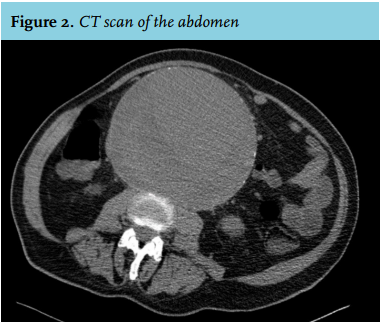

Our suspected diagnosis was confirmed by a CT scan of the abdomen, showing an infrarenal aneurysm of the abdominal aorta (AAA) with a diameter of 17 cm, causing a mechanical ileus (figure 2).

AAAs are relatively common and potentially life-threatening.1 They are defined as a focal dilatation of an artery with at least a 50% increase over the vessel’s normal diameter. Therefore, an infrarenal aorta that is 3 cm or more is considered an AAA. An AAA of 17 cm is an exceptional finding, because the risk of rupture increases strongly with increasing diameter.2 AAAs with a diameter > 8 cm are associated with a yearly chance of rupture of 30-50%.2 AAAs generally affect elderly Caucasian men.3 Risk factors include smoking, chronic obstructive pulmonary disease, and increased body mass index. In addition, individuals with first-degree relatives with AAAs are at increased risk.